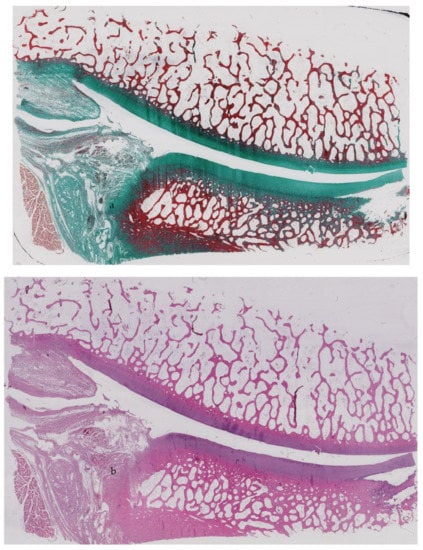

3.3. Histological Assessment